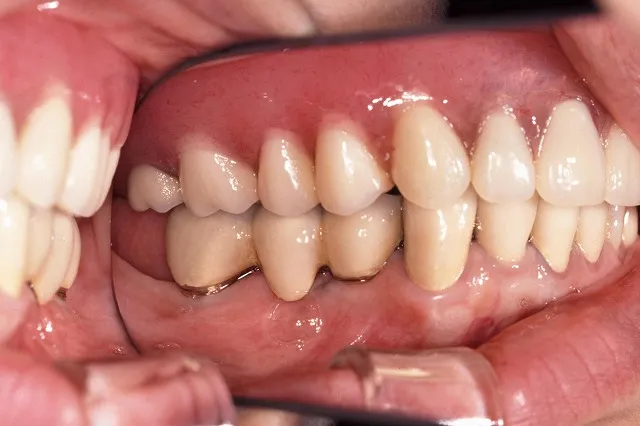

■治療前